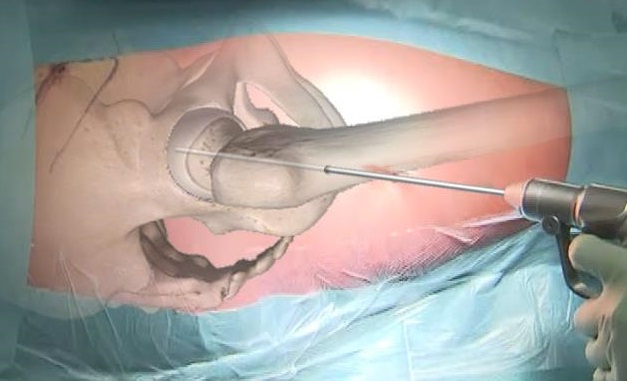

Tempo di riparazione articolare artroscopica e medicina rigenerativa

Negli stadi di osteonecrosi ove è già presente un danno condrale dovuto all’infarto osseo è neccessario associare il tempo di riparazione articolare.

Tale procedura artroscopica deve essere eseguita da un chirurgo esperto che riconosca la migliore tecnica di medicina rigenerativa da applicare e che possa inoltre ridurre al minimo il tempo chirurgico.

Tramite due accessi di circa 1 cm si visualizza direttamente la cartilagine articolare, il labrum acetabolare e le lesioni.

Le procedure applicabili hanno l’obiettivo di regolarizzare e riparare i danni per preservare l’articolazione e diminuire il dolore.

In base alla sede della lesione, alle dimensioni ed alle caratteristiche del paziente varie tecniche di medicina rigenerativa vengono infine applicate per determinare uno stimolo biologico riparativo sia all’osso subcondrale che al danno cartilagineo.